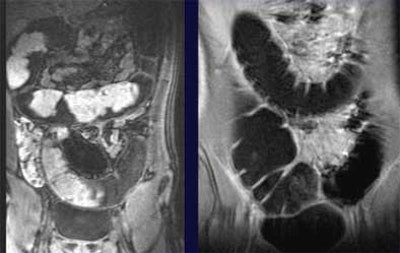

The images confirmed that the fecal material, bright without tagging, had been darkened by the oral barium to the point where it was indistinguishable from the water enema.

"There is optimal contrast resolution between the colonic lumen, that appears homogeneously dark, and the colonic wall," Paolantonio said. "The normal wall thickness was 100 mm. We looked for thickening of the colonic wall, we looked for (abnormalities) of the mucosal layer like pseudopolyps and like loss of haustral folds, and for parenchymal enhancement. Here you can see in this T2-weighted sequence some thickening of the colonic wall of the transverse colon with some pseudopolyps. These irregularities are shown also in this 3D reconstruction, with a good correlation to endoscopic view."

| Unprepped dark-lumen MR colonography technique shows normal subjects (colonic wall thickness < 3 mm) without (left) and with (right) fecal tagging. Fecal material visible in colon at left darkens to become indistinguishable from the water enema after fecal tagging, right, permitting assessment of the colon wall for IBD. Images courtesy of Dr. Pasquale Paolantonio. |